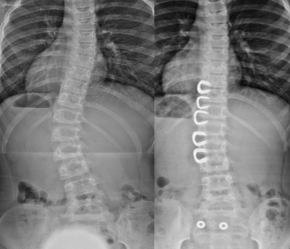

8-year-old girl with a 40° scoliosis. As an alternative to several years of corset therapy, this patient was treated with spinal braces. Already 1 year postoperatively there was an almost complete correction of scoliosis without the need for fusion.